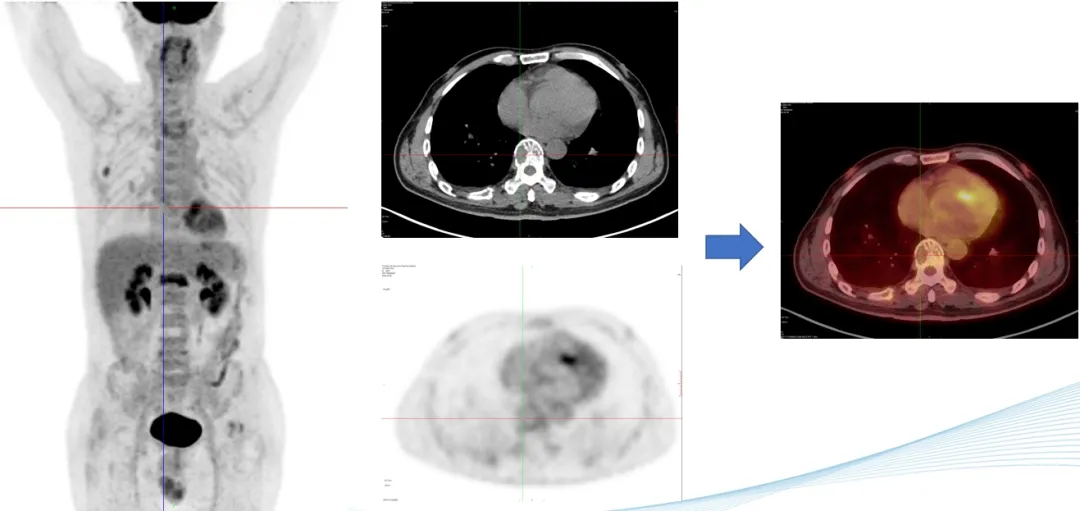

部分PET-CT影像图

前海人寿南宁医院核医学科PET-CT中心的阅片团队对扫描获得的李叔叔的全身影像图片反复多次的观察与比对,凭借着二十几年丰富的阅片经验,核医学科陈伟华主任发现,李叔叔肩胛骨、腰椎多处、双侧髂骨、左侧耻骨等出现了斑点片状、虫蚀样等形态溶骨性骨破坏,考虑恶性病变,多发性骨髓瘤可能性大,建议李叔叔立即进行骨髓穿刺检查。病理学检查结果证实了陈主任的影像诊断。腰痛的罪魁祸首终于找到,目前李叔叔已针对病因进行精准联合化疗。

多发性骨髓瘤(MM)是一种克隆性浆细胞异常增生的恶性疾病,多发于老年人,其发病率居恶性血液病的第二位,目前在我国其发病率呈逐年上升的趋势。PET-CT显像能够在分子水平上提供恶性肿瘤的增殖和代谢情况等信息,并可先于骨质结构变化,在早期发现骨髓的浸润和骨骼代谢的变化,这对于MM骨病的早期诊断具有重要意义。已有的研究结果表明,其在MM的诊断、分期、疗效监测和预后评估等方面具有重要意义。

18F-FDG是一种与葡萄糖结构相似的放射性核素标记化合物,其可进入细胞并滞留在细胞内。当葡萄糖代谢处于平衡状态时,18F-FDG在细胞内的滞留量与细胞消耗的葡萄糖量大体一致,通过18F示踪可反映机体器官、组织和细胞的葡萄糖分布和摄取水平。MM的骨骼和髓外浸润病灶具有高代谢的特点,故在18F-FDG PET-CT显像中显示为高摄取。